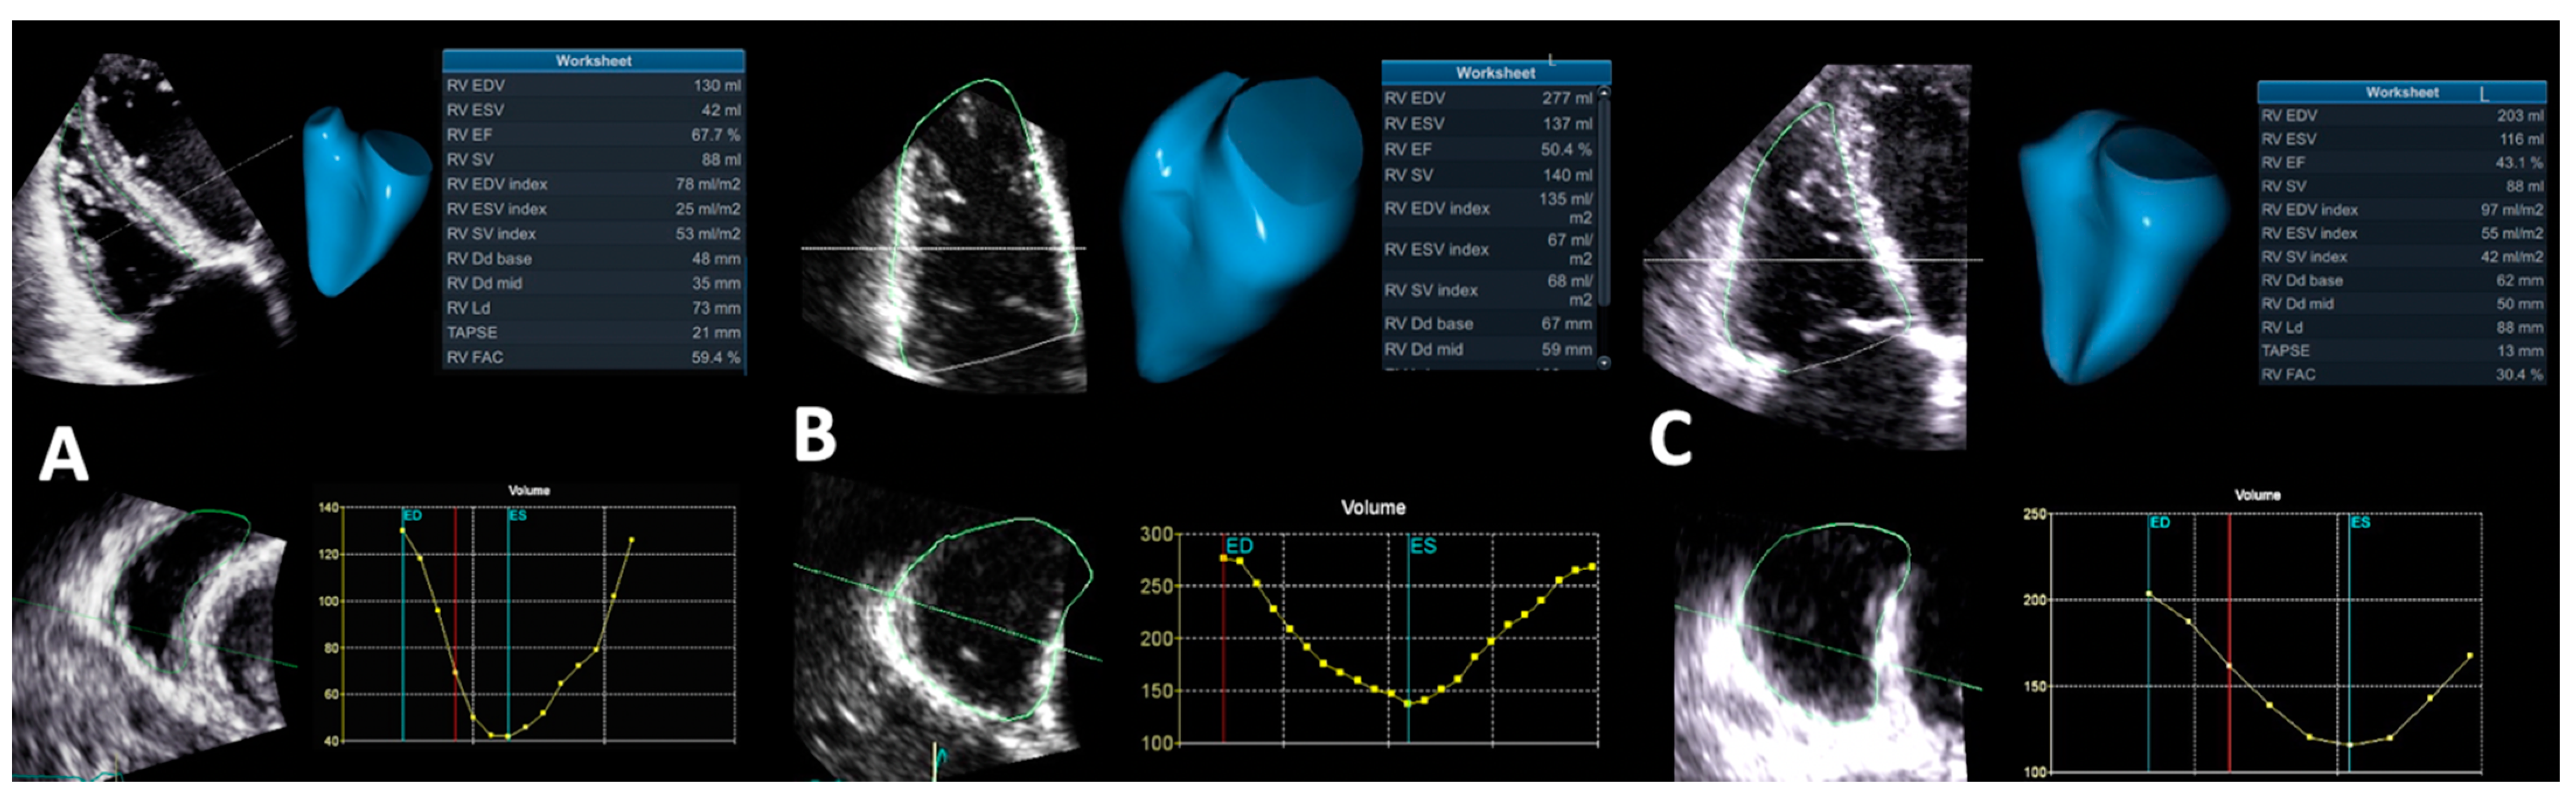

4.1.6. Right Ventricular Ejection Fraction by Three-Dimensional Echocardiography